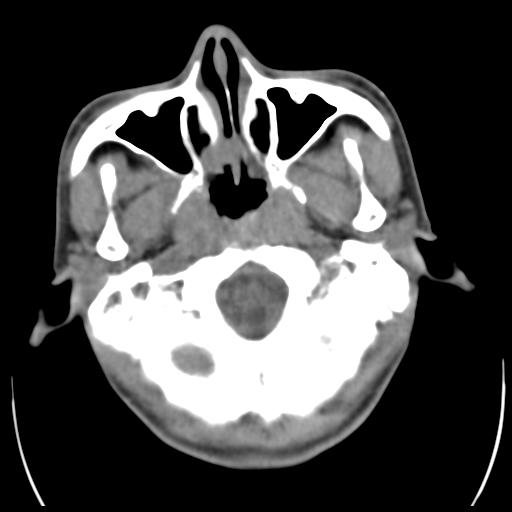

35m 鼻子时不时流血,头及右侧面部痛,颈部淋巴结未见明显大

骨窗

蝶窦,后组筛窦及鼻咽部团块状软组织影,骨壁破坏,病变较广泛。考虑恶性肉芽肿。建议活检。

颅底骨质明显破坏 支持鼻咽癌 但病灶的边缘毛糙 不能除外炎性

蝶窦,后组筛窦及鼻咽部团块状软组织影,骨壁破坏,病变较广泛。考虑炎性肉芽肿性病变可能。建议活检。